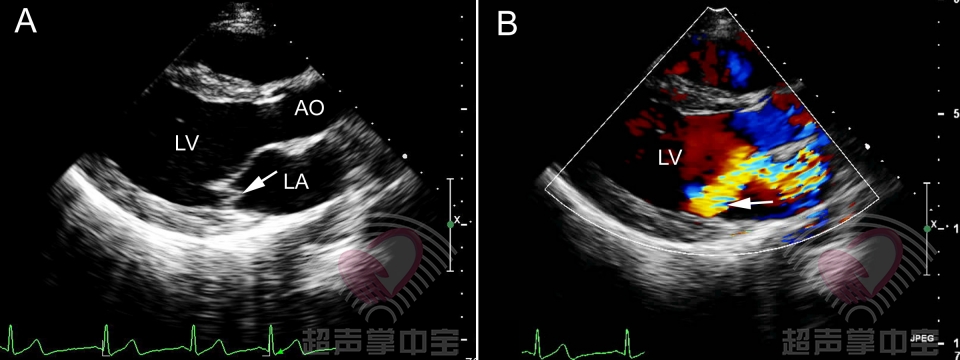

心脏瓣膜病超声诊断_二尖瓣

二尖瓣狭窄:你想知道的超声知识点都在

三,二尖瓣脱垂 | 超声掌中宝

孔令秋二尖瓣收缩期杂音相关疾病的超声表现